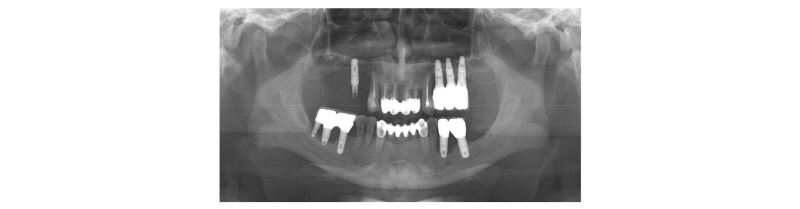

골유도 재생술을 시행한 후 5개월이 지난 후에 임플란트를 식립하도록 하였다. 우측 하악 구치부에 시행한 비흡수성 차폐막을 제거한 후(Fig. 9A~9C), 직경 5 mm 임플란트 2개를 각각 #46, #47 부위에 식립하였다(Fig. 9D~9F). 골질은 D1 정도였고 초기 고정도 잘 이루어졌다. 그 다음에는 우측 상악 구치부 수술을 진행하였다. Titanium mesh를 제거한 후(Fig. 10A~10D), #14, #15 부위에는 직경 4.5 mm 의 임플란트를 식립하였고, #16 부위에는 직경 5 mm 임플란트를 식립하였다(Fig. 10E, 10F). 골질은 D3 정도였으나 초기 고정을 얻는 데에는 큰 무리가 없었다.